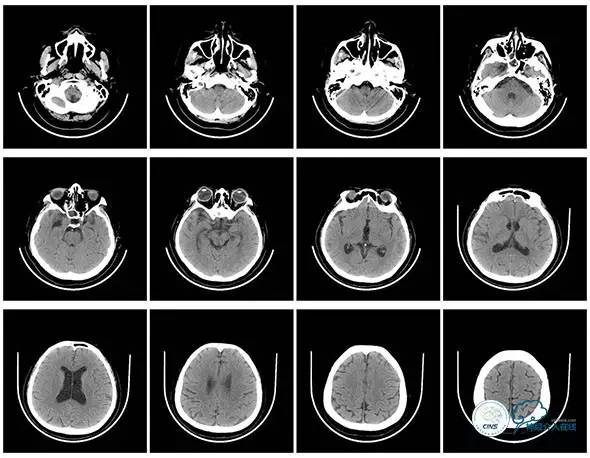

头颅CT

头颅CT(2017.6.20)

颞骨CT(2017.6.20)